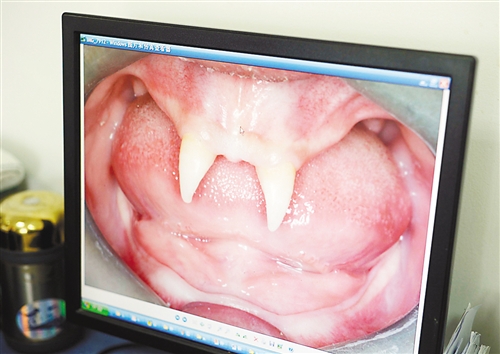

12月18日,16歲的張成(化名)從小到大,只有上顎部分有兩顆牙,看上去更像長著一對獠牙。 記者熊明攝

重慶日報訊 每個人都有牙齒,但對16歲的張成(化名)來說,從小到大,他只有上顎部分有兩顆牙,看上去更像長著一對獠牙,這讓他很自卑又易怒。12月18日,在母親的陪同下,他來到三軍醫大西南醫院求助。經醫生檢查,發現張成患有一種罕見的基因病。

張成是貴州銅仁地區思南縣人,從生下來就似乎得了一種怪病,身上毛發稀少,面部發育也不好。更奇怪的是,別人家的孩子都長牙吃東西了,他卻一直長不出牙齒,最后只在上顎部分冒出兩顆比較突出且對稱的牙齒,看起來就像一對獠牙。